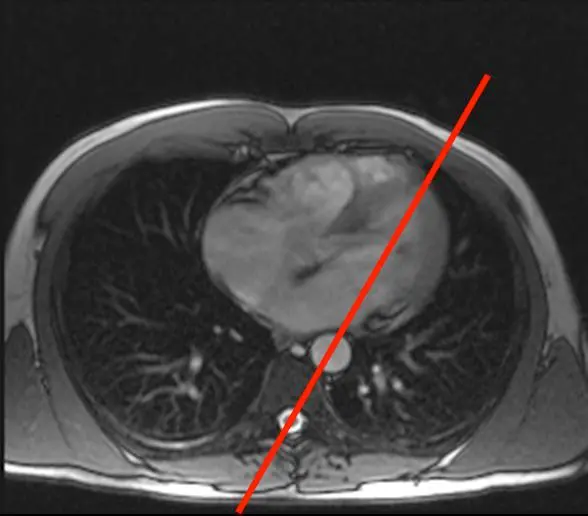

- Step 1. Scouts and planning views (VLA, HLA)

- We begin with the transverse LAX view and position the line marker dissecting the apex and the middle of the mitral valve (where the two leaflets meet) → results in a vertical LAX (VLA) view, aka pseudo 2 chamber (p2CH) view